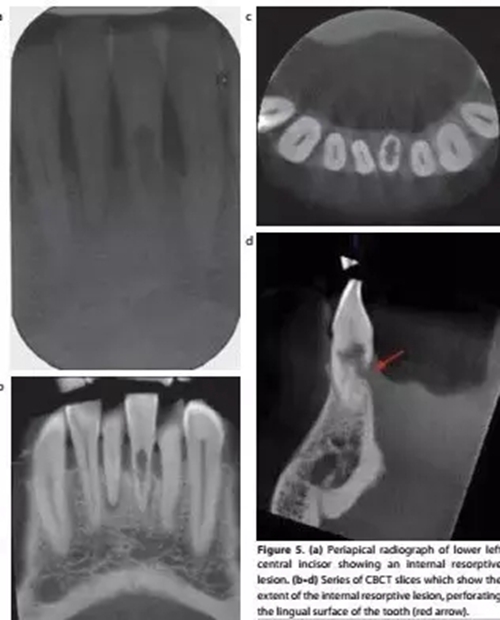

a-根尖片顯示31牙根吸收;b,c,d-對(duì)31的CBCT掃描清楚顯示內(nèi)吸收范圍和程度,舌側(cè)牙根已穿通;

對(duì)于牙根吸收的情況,CBCT能反映病損來源、位置和進(jìn)展程度,有助于治療方案的制定。例如外吸收一般只能通過手術(shù)進(jìn)行干預(yù),而內(nèi)吸收則需要根據(jù)程度來判斷保留價(jià)值。